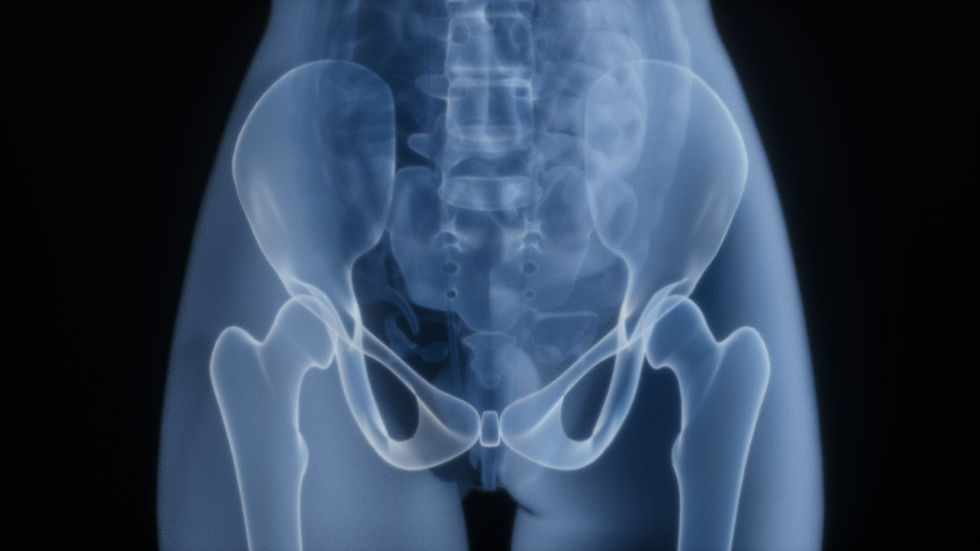

Femoroacetabular impingement (FAI) happens when the ball and socket of the hip compress soft tissue structures during certain movements — most commonly end-range hip flexion combined with rotation. In dance, this shows up during high extensions, deep pliés, turnout work, and anything that asks the hip to move toward its limits.

There are two bony presentations: CAM impingement (extra bone at the femoral head) and Pincer impingement (extra coverage at the acetabulum). Many dancers have a combination. Some have no bony abnormality at all but still impinge — because the issue is movement pattern and load, not anatomy.

The presence of FAI on imaging does not predict pain. Plenty of dancers have FAI on MRI and no symptoms. Plenty of others have pain with no structural findings. What determines symptoms is how the hip is being loaded — not what it looks like on a scan.